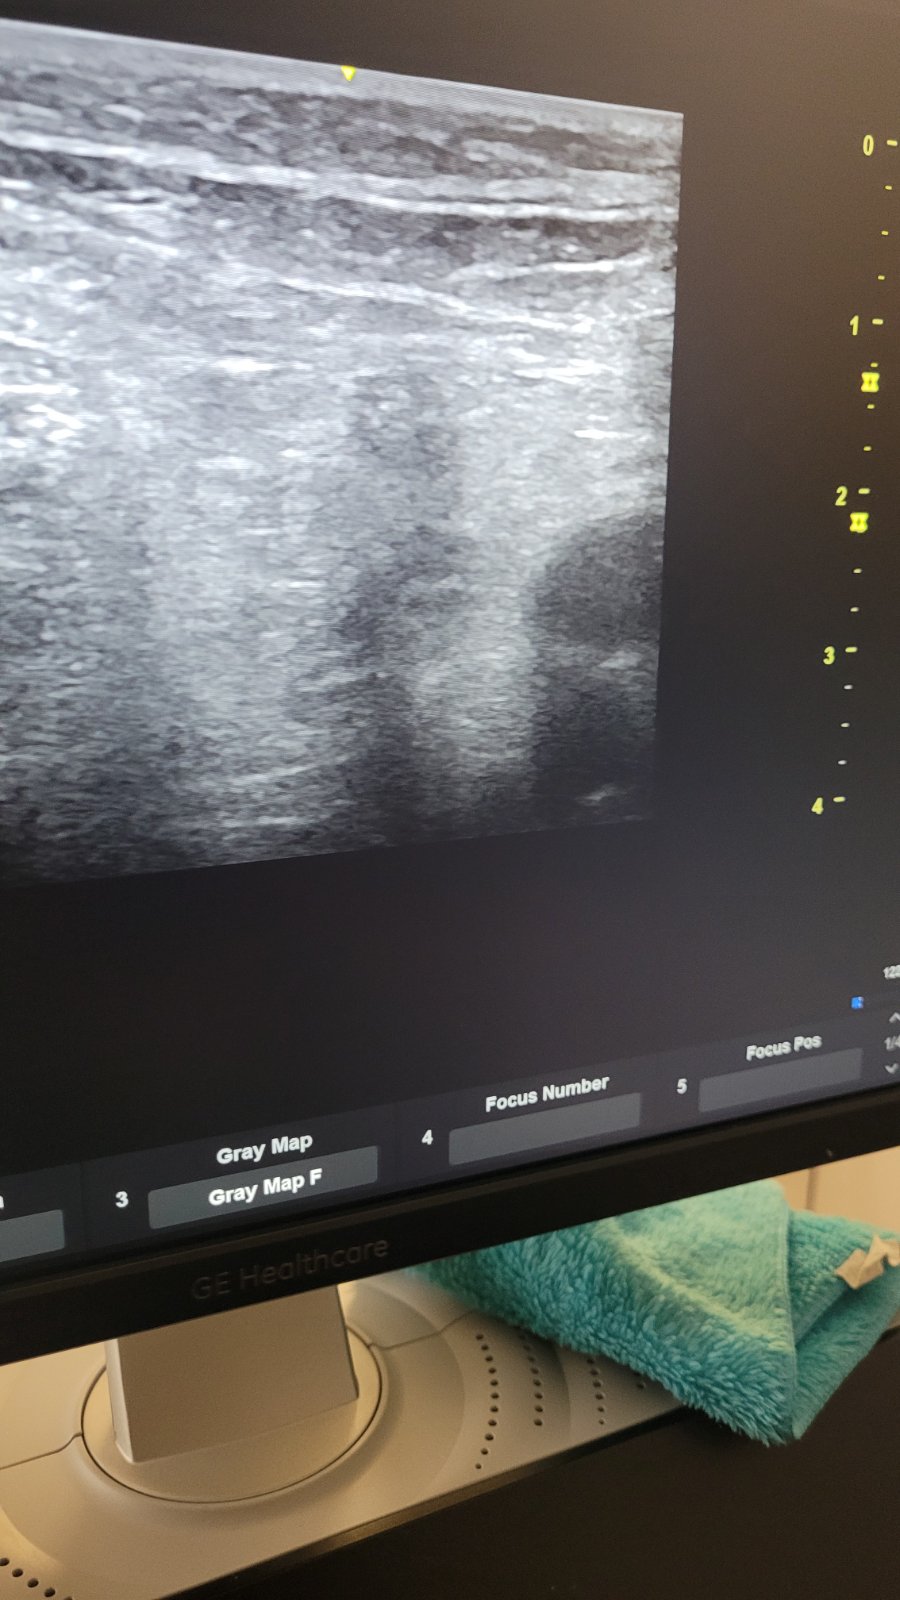

Program je osmišljen u hibridnom formatu, spajajući online teorijska predavanja sa praktičnim radionicama. Polaznici su imali priliku da stiču teorijska znanja iz ultrazvučne dijagnostike putem interaktivnih online predavanja, nakon čega su ih primijenili u kliničkoj praksi tokom trodnevnih radionica u JZU Bolnica “Sveti Vračevi” Bijeljina. Polaznici su dobili priliku da primijene stečena znanja u kliničkoj praksi, usavršavaju tehnike pregleda i razmjenjuju iskustva sa kolegama.